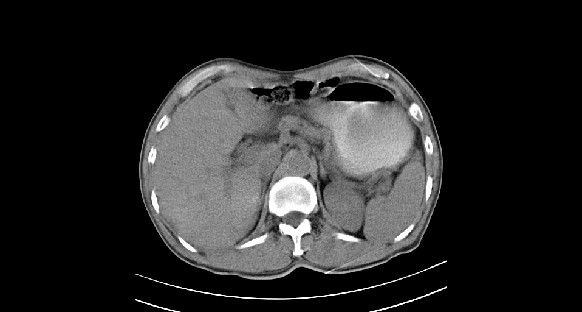

男性,70岁,体检b超发现左肾占位,请各位战友发表一下观点

左肾有两个病灶,且较大的病灶内可见点状钙化灶,增强扫描边缘也是呈渐进性强化,中央部分未见明显强化